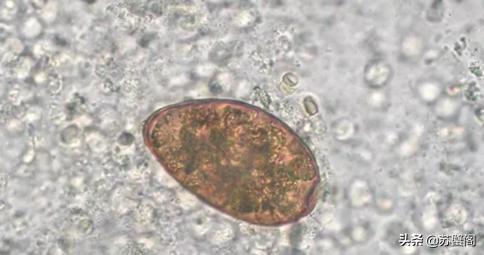

痰液中的肺吸虫卵Q1